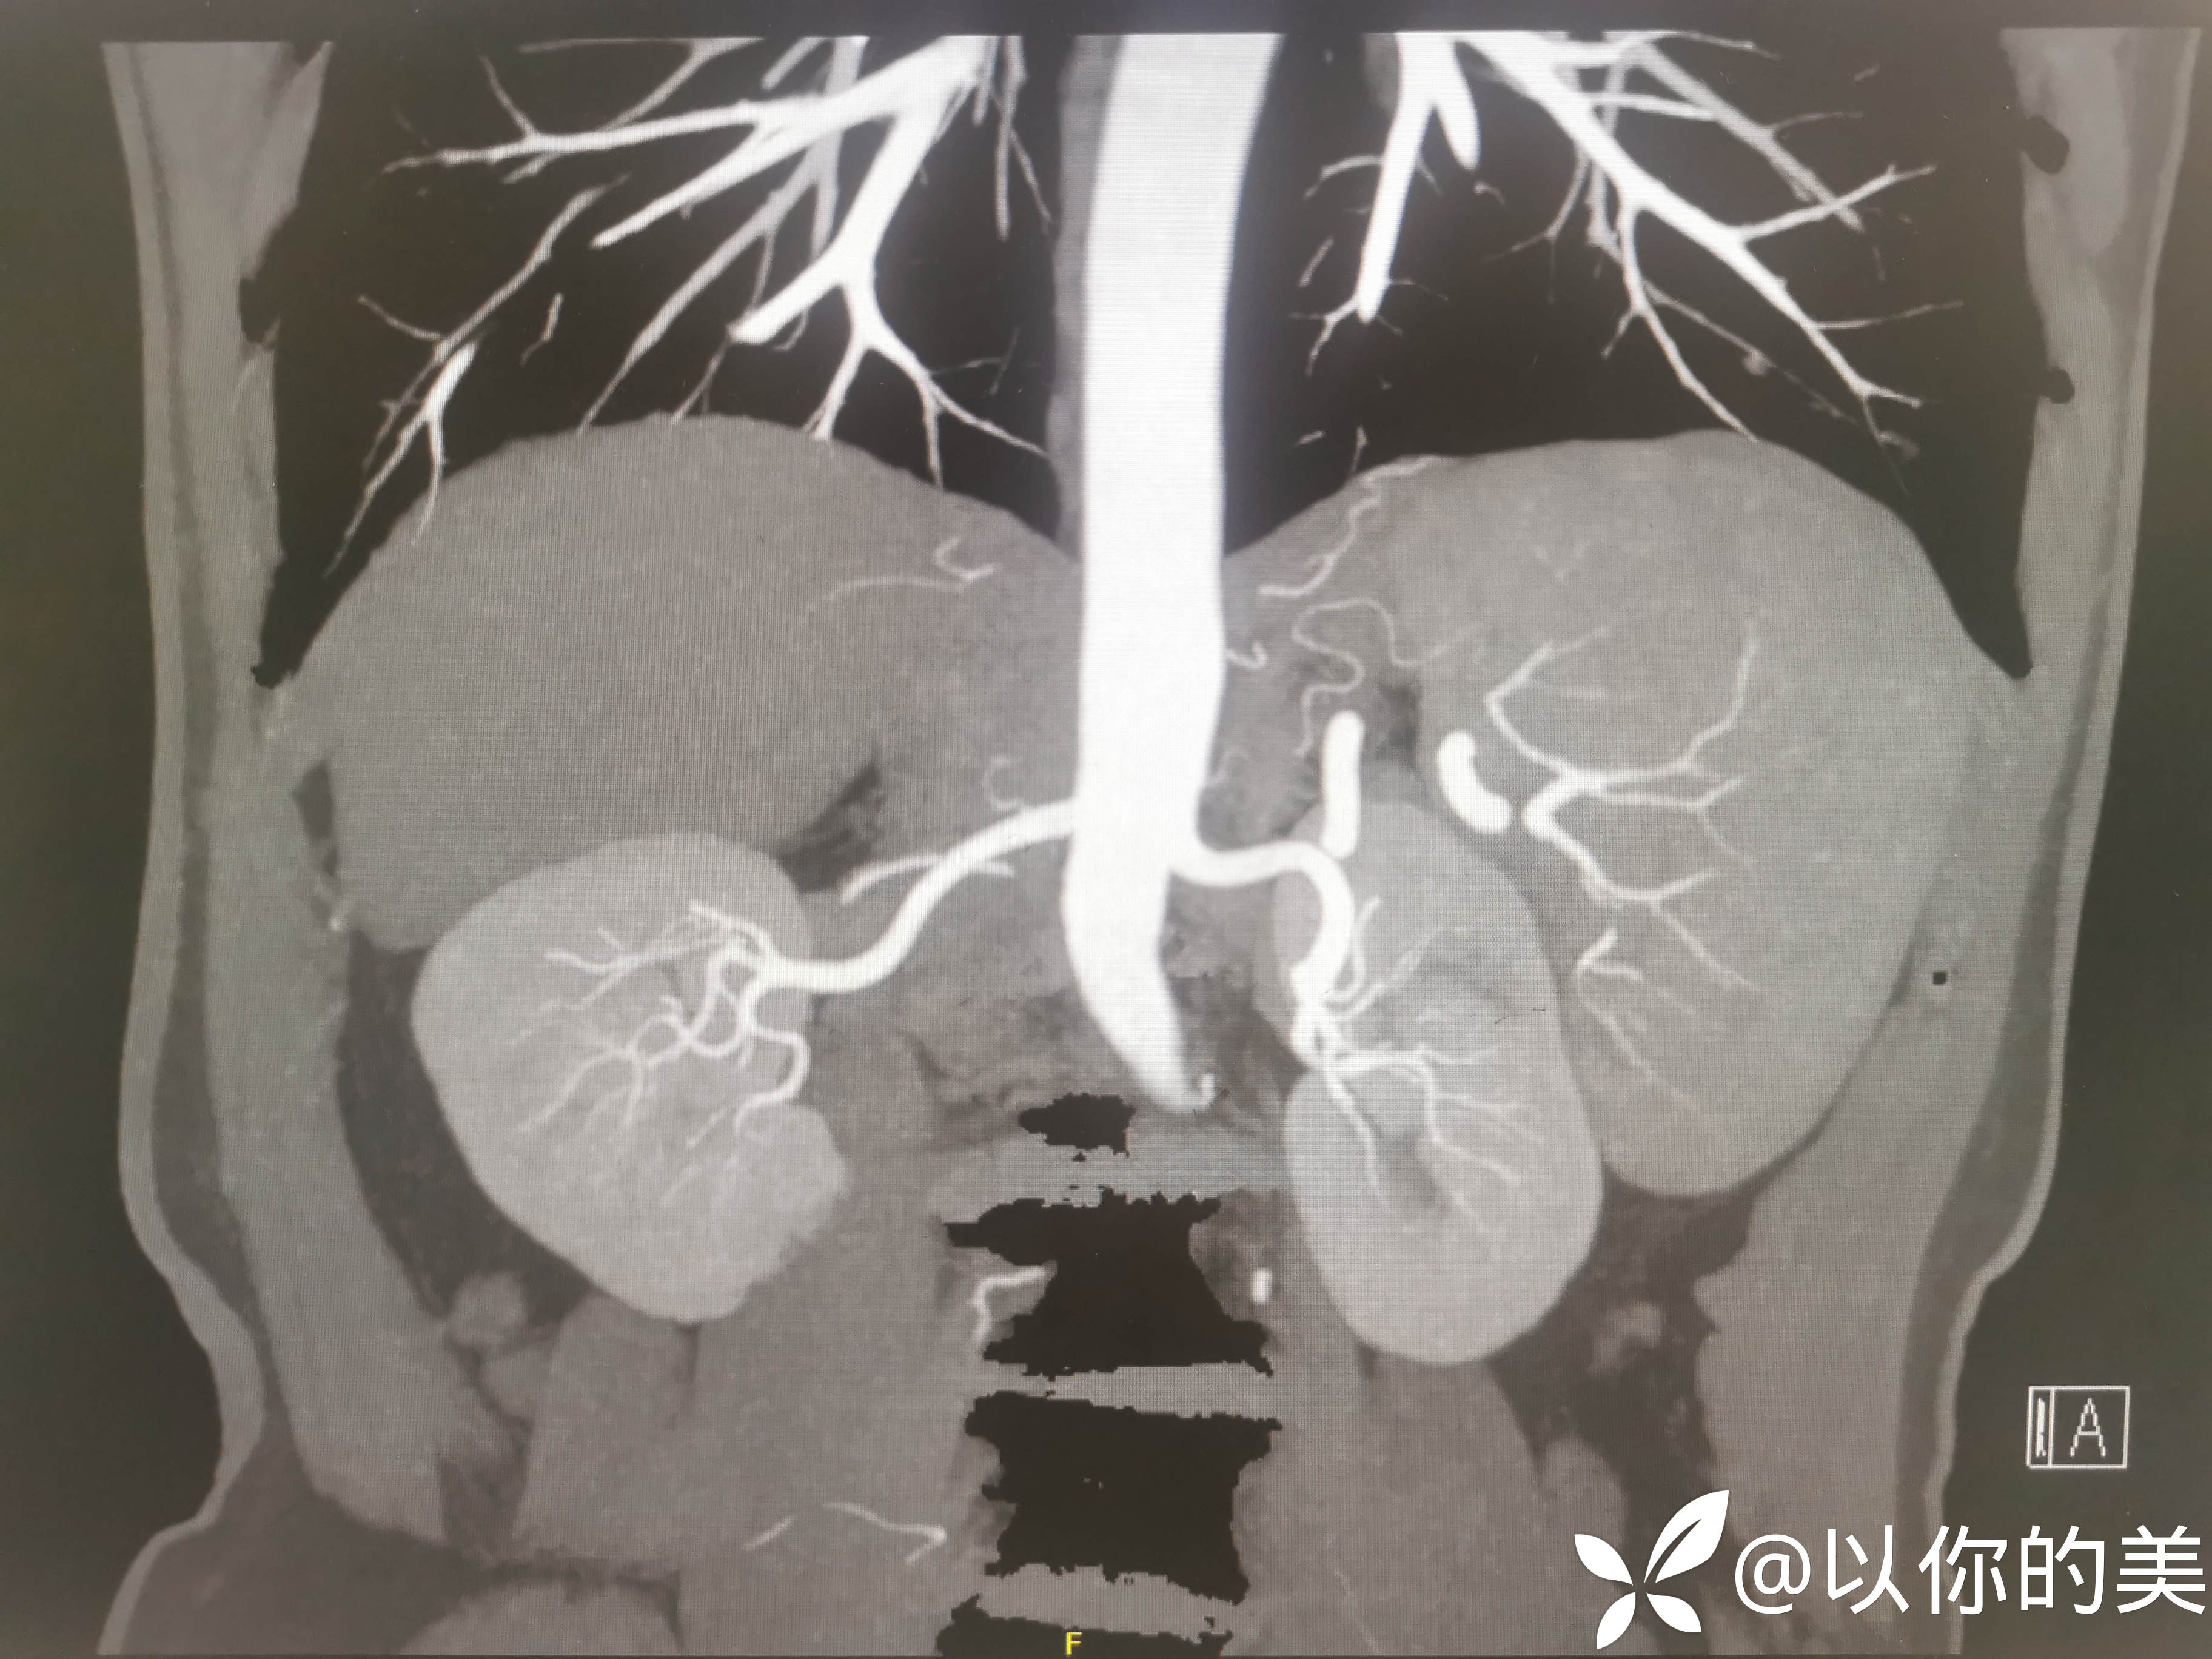

肾血管CTA:

肾血管CTA有无异常,行肾血管CTA意义何在?